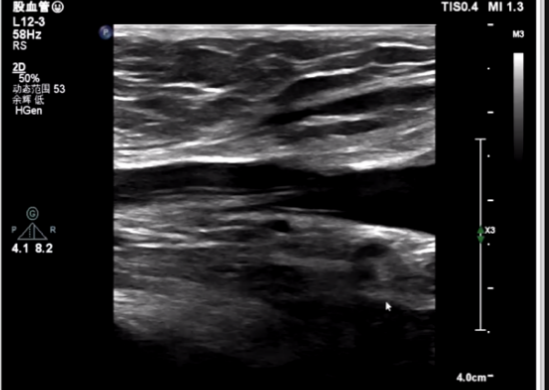

该病例为70岁女性患者,间歇胸闷气短17年,反复住院药物保守治疗,效果不佳,10日前症状加重,伴有胸痛、头晕、黑朦,双下肢水肿,转于我院就诊。经检查分析,诊断为重度主动脉瓣狭窄,风心病,患者主动脉瓣叶增厚,左心耳血栓,左冠开口小于10mm,存在一定冠脉阻塞风险,右侧股动脉分叉在股骨头中点,左侧股动脉分叉高于股骨头中点,双侧髂外动脉最小直径小于5.5mm,主动脉弓角偏大,对血管介入造成难点,同时易引起血管并发症,手术难度大。经杨毅宁教授团队充分评估,对患者采取全麻下经食道超声监测,选用目前行业最低入路要求美敦力递送系统配合自带内联鞘进行介入。

根据术前CT分析,结合患者瓣膜钙化情况,决定预装Evolut PRO 26mm瓣膜,采用超声引导下穿刺,确保入路精准,对血管损伤最小。